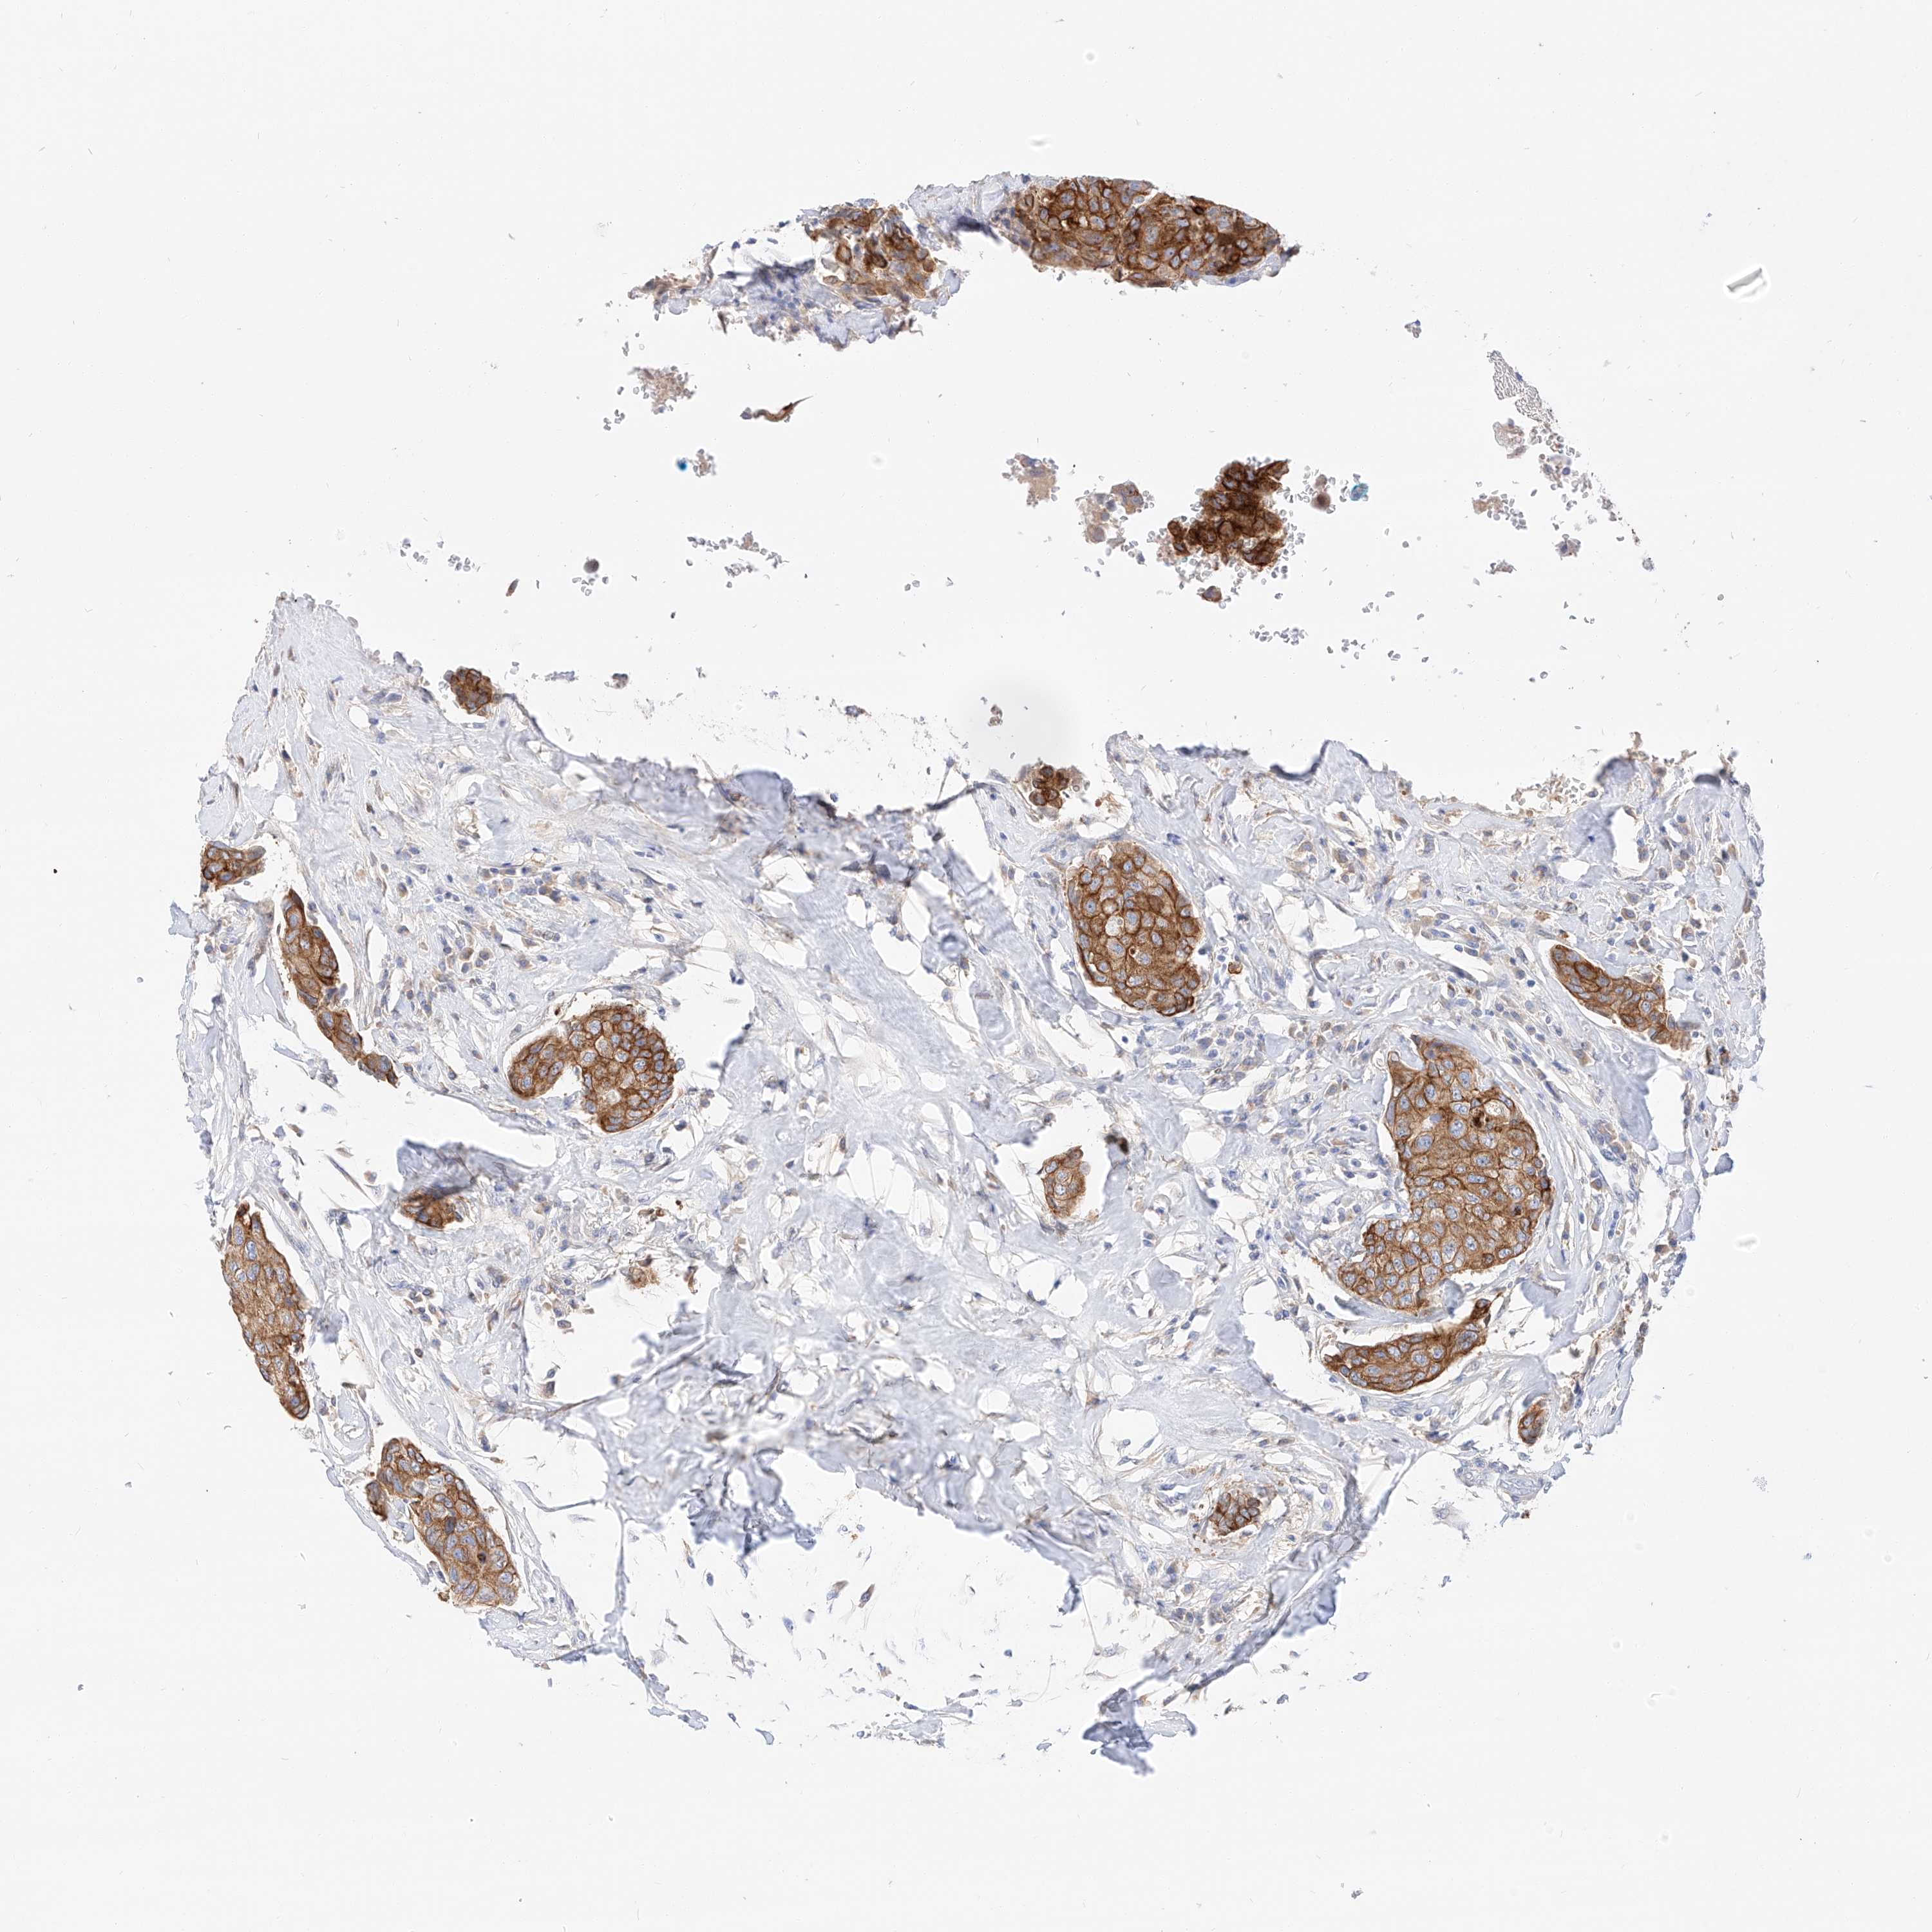

CANCER BREAST CANCER Show tissue menu

BRCA TCGA BRCA VALIDATION PROTEIN EXPRESSION